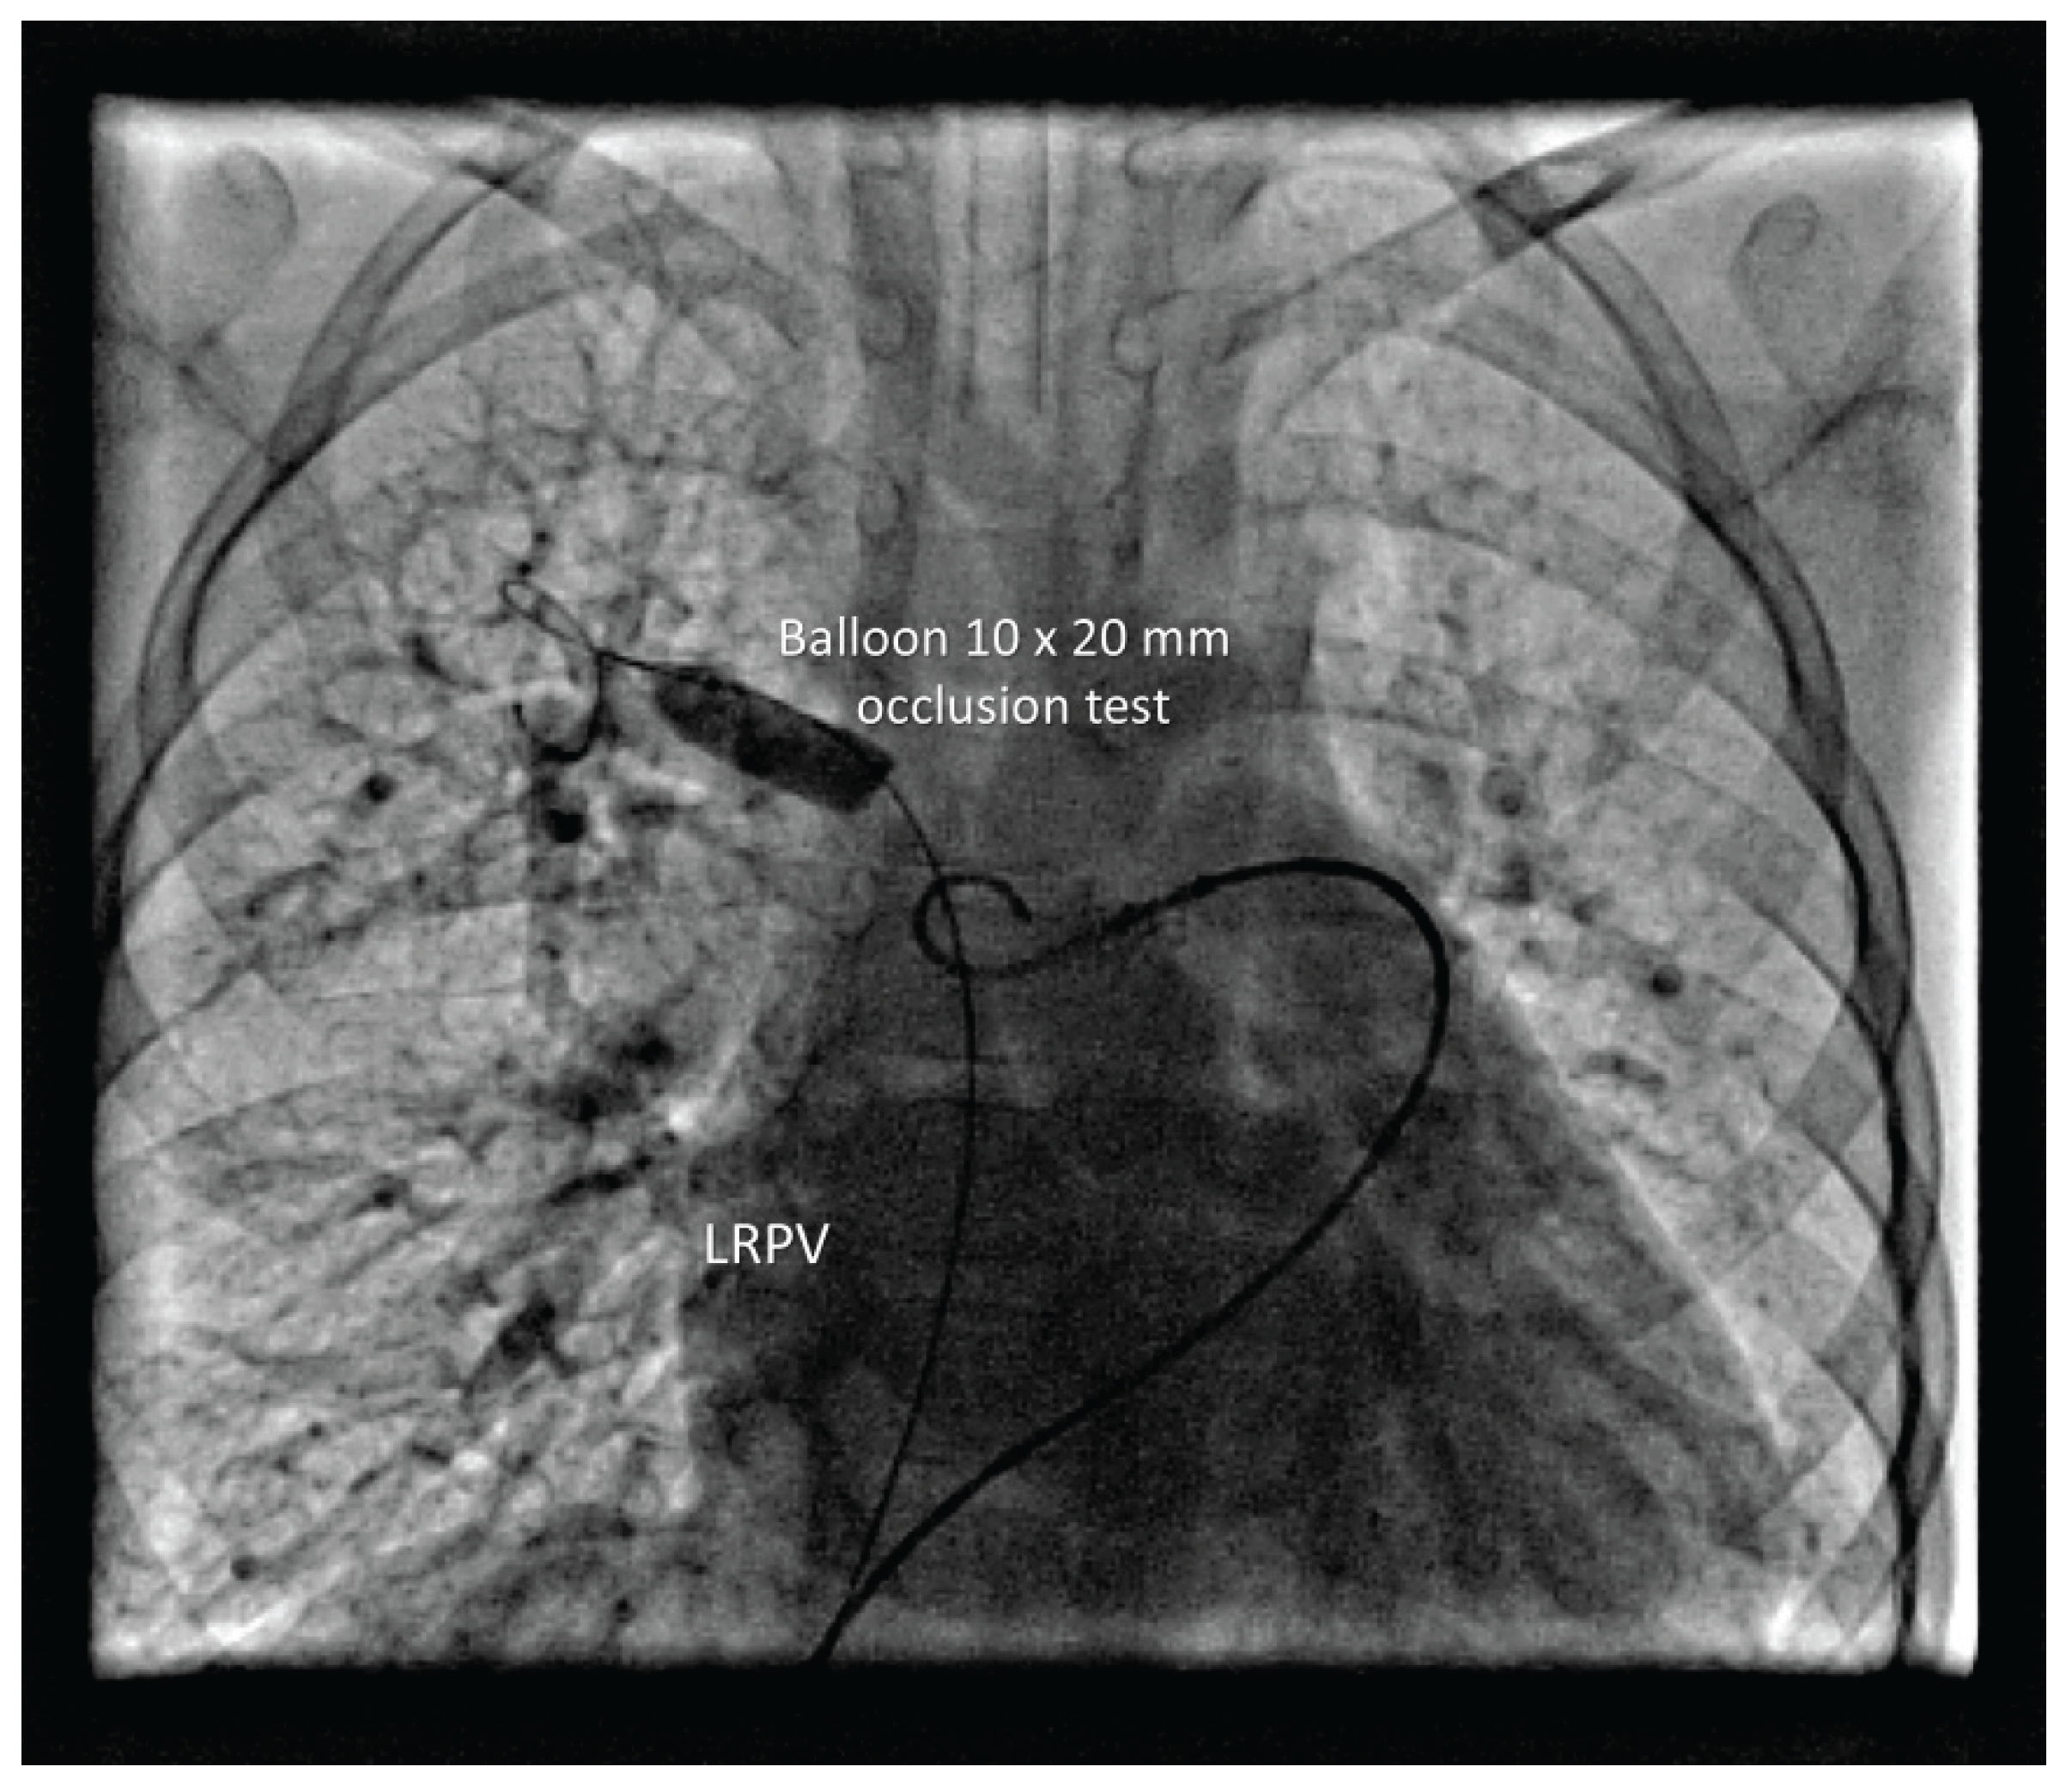

The RLPV drained normally. A 5 Fr sheath was placed in the left femoral vein. Balloon occlusion testing was performed using a 10 × 20 mm balloon in RUPV and LUPV followed by selective left and right PA angiography, respectively (Figure 2). No residual anomalous venous pathways were visualized in either upper pulmonary lobe. Pulmonary venous return drained freely and rapidly into the left atrium, with no significant increase in MPA pressure during prolonged balloon occlusion. A 12 mm Amplatzer Vascular Plug II was deployed in the RUPV (Figure 3).

Figure 2. Balloon test occlusion of the RUPV.